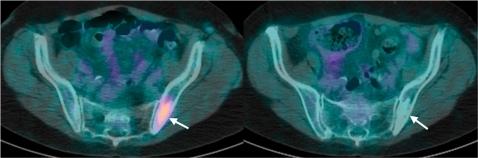

Drug development continues to face challenges to successfully progress the most promising drug candidates through the stages of clinical trials. Given the increasing cost to develop a drug, methods are required to characterise early drug efficacy and safety. Imaging techniques are increasingly used in oncological clinical trials to provide evidence for decision making. With the application of conventional morphological imaging techniques and standardised response criteria based on tumour size measurements, imaging continues to be used to define key study end points. However, functional imaging techniques are likely to play an important role in the evaluation of novel therapeutics, although how these methods are to be optimally applied has yet to be clearly established. The specific challenges of standardising multi-centre imaging in the context of clinical trials are highlighted, including the processes for image acquisition, data analysis and radiological review.